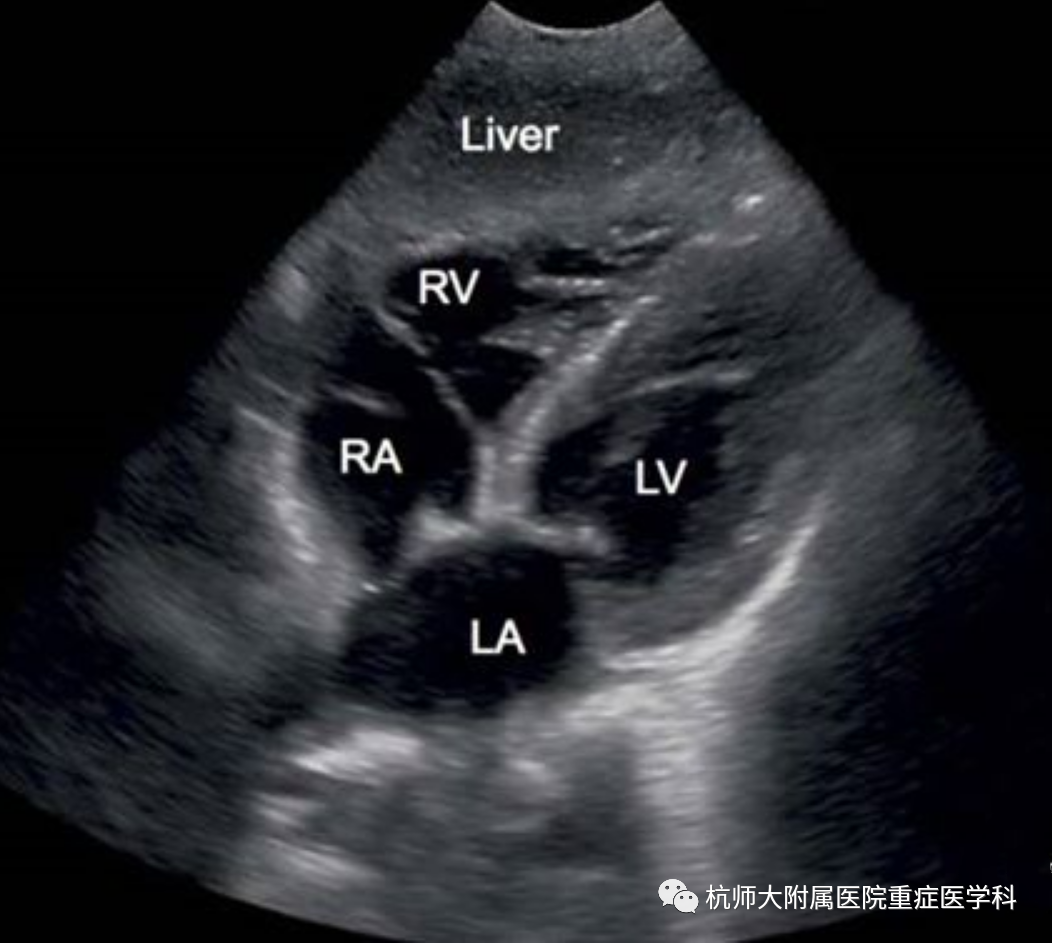

g.剑突下四腔心切面:位置选择:剑突下,超声探头声束朝向与房间隔平行,超声探头标记点指向左侧;操作中:(1)滑:超声探头从腹部向剑突下水平滑动;超声探头标记点指向受检者左侧;(2)倾:超声探头从水平方向缓慢向上倾斜,显露心脏;

什么是超声容积探头重症心脏超声图像的获取_https://www.jmylbn.com_新闻资讯_第25张什么是超声容积探头重症心脏超声图像的获取_https://www.jmylbn.com_新闻资讯_第26张

主要评估内容:(1)心包积液检查;(2)观察四个腔室及二尖瓣、三尖瓣的结构与运动;(3)评估右心室室壁厚度、房间隔缺损的最佳切面。